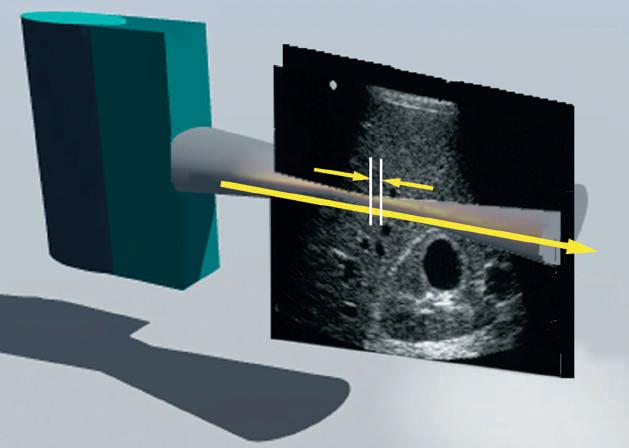

FIG. 1.22 Elastography. (A) Strain elastography (SE), and (B) shear wave elastography (SWE). Strain elastograms are images of tissue stiffness generated by analysis of speckle displacements before and after mechanical compression of tissue. The precompression frame is compared to a frame obtained after compression. In this example, the lesion is compressed much less than the surrounding tissue, indicating relative stiffness. SE is not quantitative and indicates only the relative hardness or softness of lesions compared to their surroundings. In SWE (B) high-intensity compression pulses from the transducer are focused on an area of interest, resulting in the generation of low-frequency shear waves. Speckle displacement resulting from shear (transverse) waves is tracked with multiple imaging frames in order to estimate shear wave velocity. Shear wave velocity is directly related to Young modulus, permitting a quantitative estimate of tissue stiffness.

Ultrasound-based elastography permits study of the elastic behavior of tissue through two general approaches (Fig. 1.22): strain elastography and shear wave elastography.

Shear Wave Elastography

Longitudinal tissue compression results in the generation of transverse shear waves12,13 (see Fig. 1.22B). In shear wave elastography, shear waves are generated by repetitive compression produced by high-intensity pulses from the ultrasound transducer (see Fig. 1.22B). In contrast to longitudinal compressional waves that propagate very quickly in the human body (≈1540 m/sec), shear waves propagate slowly (≈1-50 m/sec). Shear waves are tracked with high frame rate images to determine their velocity. The propagation velocity of shear waves is directly proportional to Young modulus and provides a quantitative estimate of tissue stiffness14,15 (Fig. 1.24).